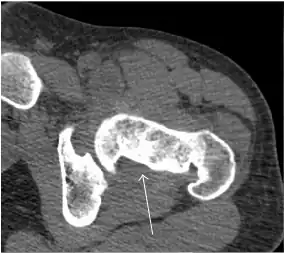

Synovial chondromatosis can be confidently diagnosed by X-ray when calcified cartilaginous chondromas are seen. However, other synovial proliferative processes, such as pigmented villonodular synovitis, require MRI for accurate diagnosis, although noncalcified synovitis can be suspected in radiographs by indirect signs, such as soft tissue swelling and/or erosions in the femoral head, femoral neck, or acetabulum (Figure 7).[1]

Figure 7:

-

Axial CT image of pigmented villonodular synovitis eroding the posterior cortex of the femoral neck.[1] -

Sagittal T2* gradient echo image showing a posterior soft tissue mass with hypointense areas secondary to hemosiderin deposition.[1] -

X-ray of synovial chondromatosis.[1] -

CT of synovial chondromatosis.[1]